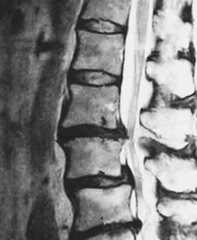

画像診断では痛みを特定出来ない

レントゲンやMRIの画像では「形の変化」しか特定できないため、骨と骨が狭くなってるから痛みが出る、骨の変形が見られるので痛みが出る、と表現されますが骨や椎間板や膝の半月板には痛みを感じる神経は通っていません!

なので、圧迫されても骨自体が変形しても、それ自体では痛みを感じる事がありません。